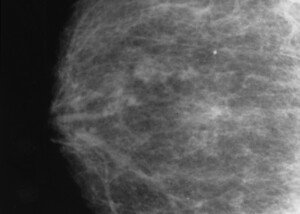

Shutterstock/A.J.Photos